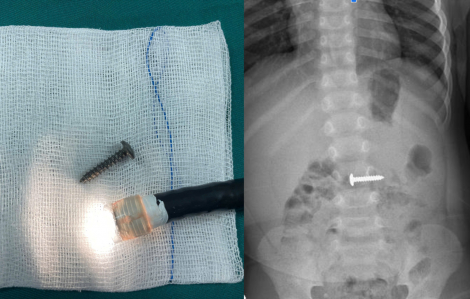

Ngày 16/3, Bệnh viện Đa khoa tỉnh Quảng Trị thông báo vừa cấp cứu thành công cho một bé trai 34 tháng tuổi nuốt phải đinh vít xoắn nhọn.